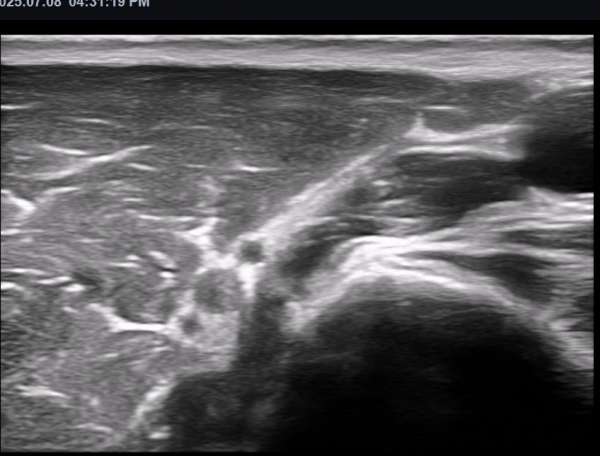

ÃÊÀ½ÆÄ ¼Ò°ß  : »ó¹Ú ³»Ãø ±ÙÀ°ÇǺνŰæ Ⱦ´Ü¸é°Ë»ç ¿¡¼­ ±ÙÀ°ÇǺνŰæÀÇ Àú¿¡ÄÚ ºÎÁ¾ÀÌ °üÂûµÈ´Ù(»çÁø 1).

±ÙÀ°ÇǺνŰæÀÇ Á¾´Ü¸é°Ë»ç¿¡¼­ ±ÙÀ°ÇǺνŰæÀÇ ±¹¼ÒÀû ÇùÂø°ú ±ÙÀ§ºÎÀÇ Àú¿¡ÄÚ ºÎÁ¾ÀÌ °üÂûµÈ´Ù

(»çÁø 4, 5, 6,7) À̰ÍÀº ½Å°æÀÇ ¿°Àü(torsion)¿¡ ºÎÇÕÇÏ´Â ¼Ò°ßÀÌ´Ù.